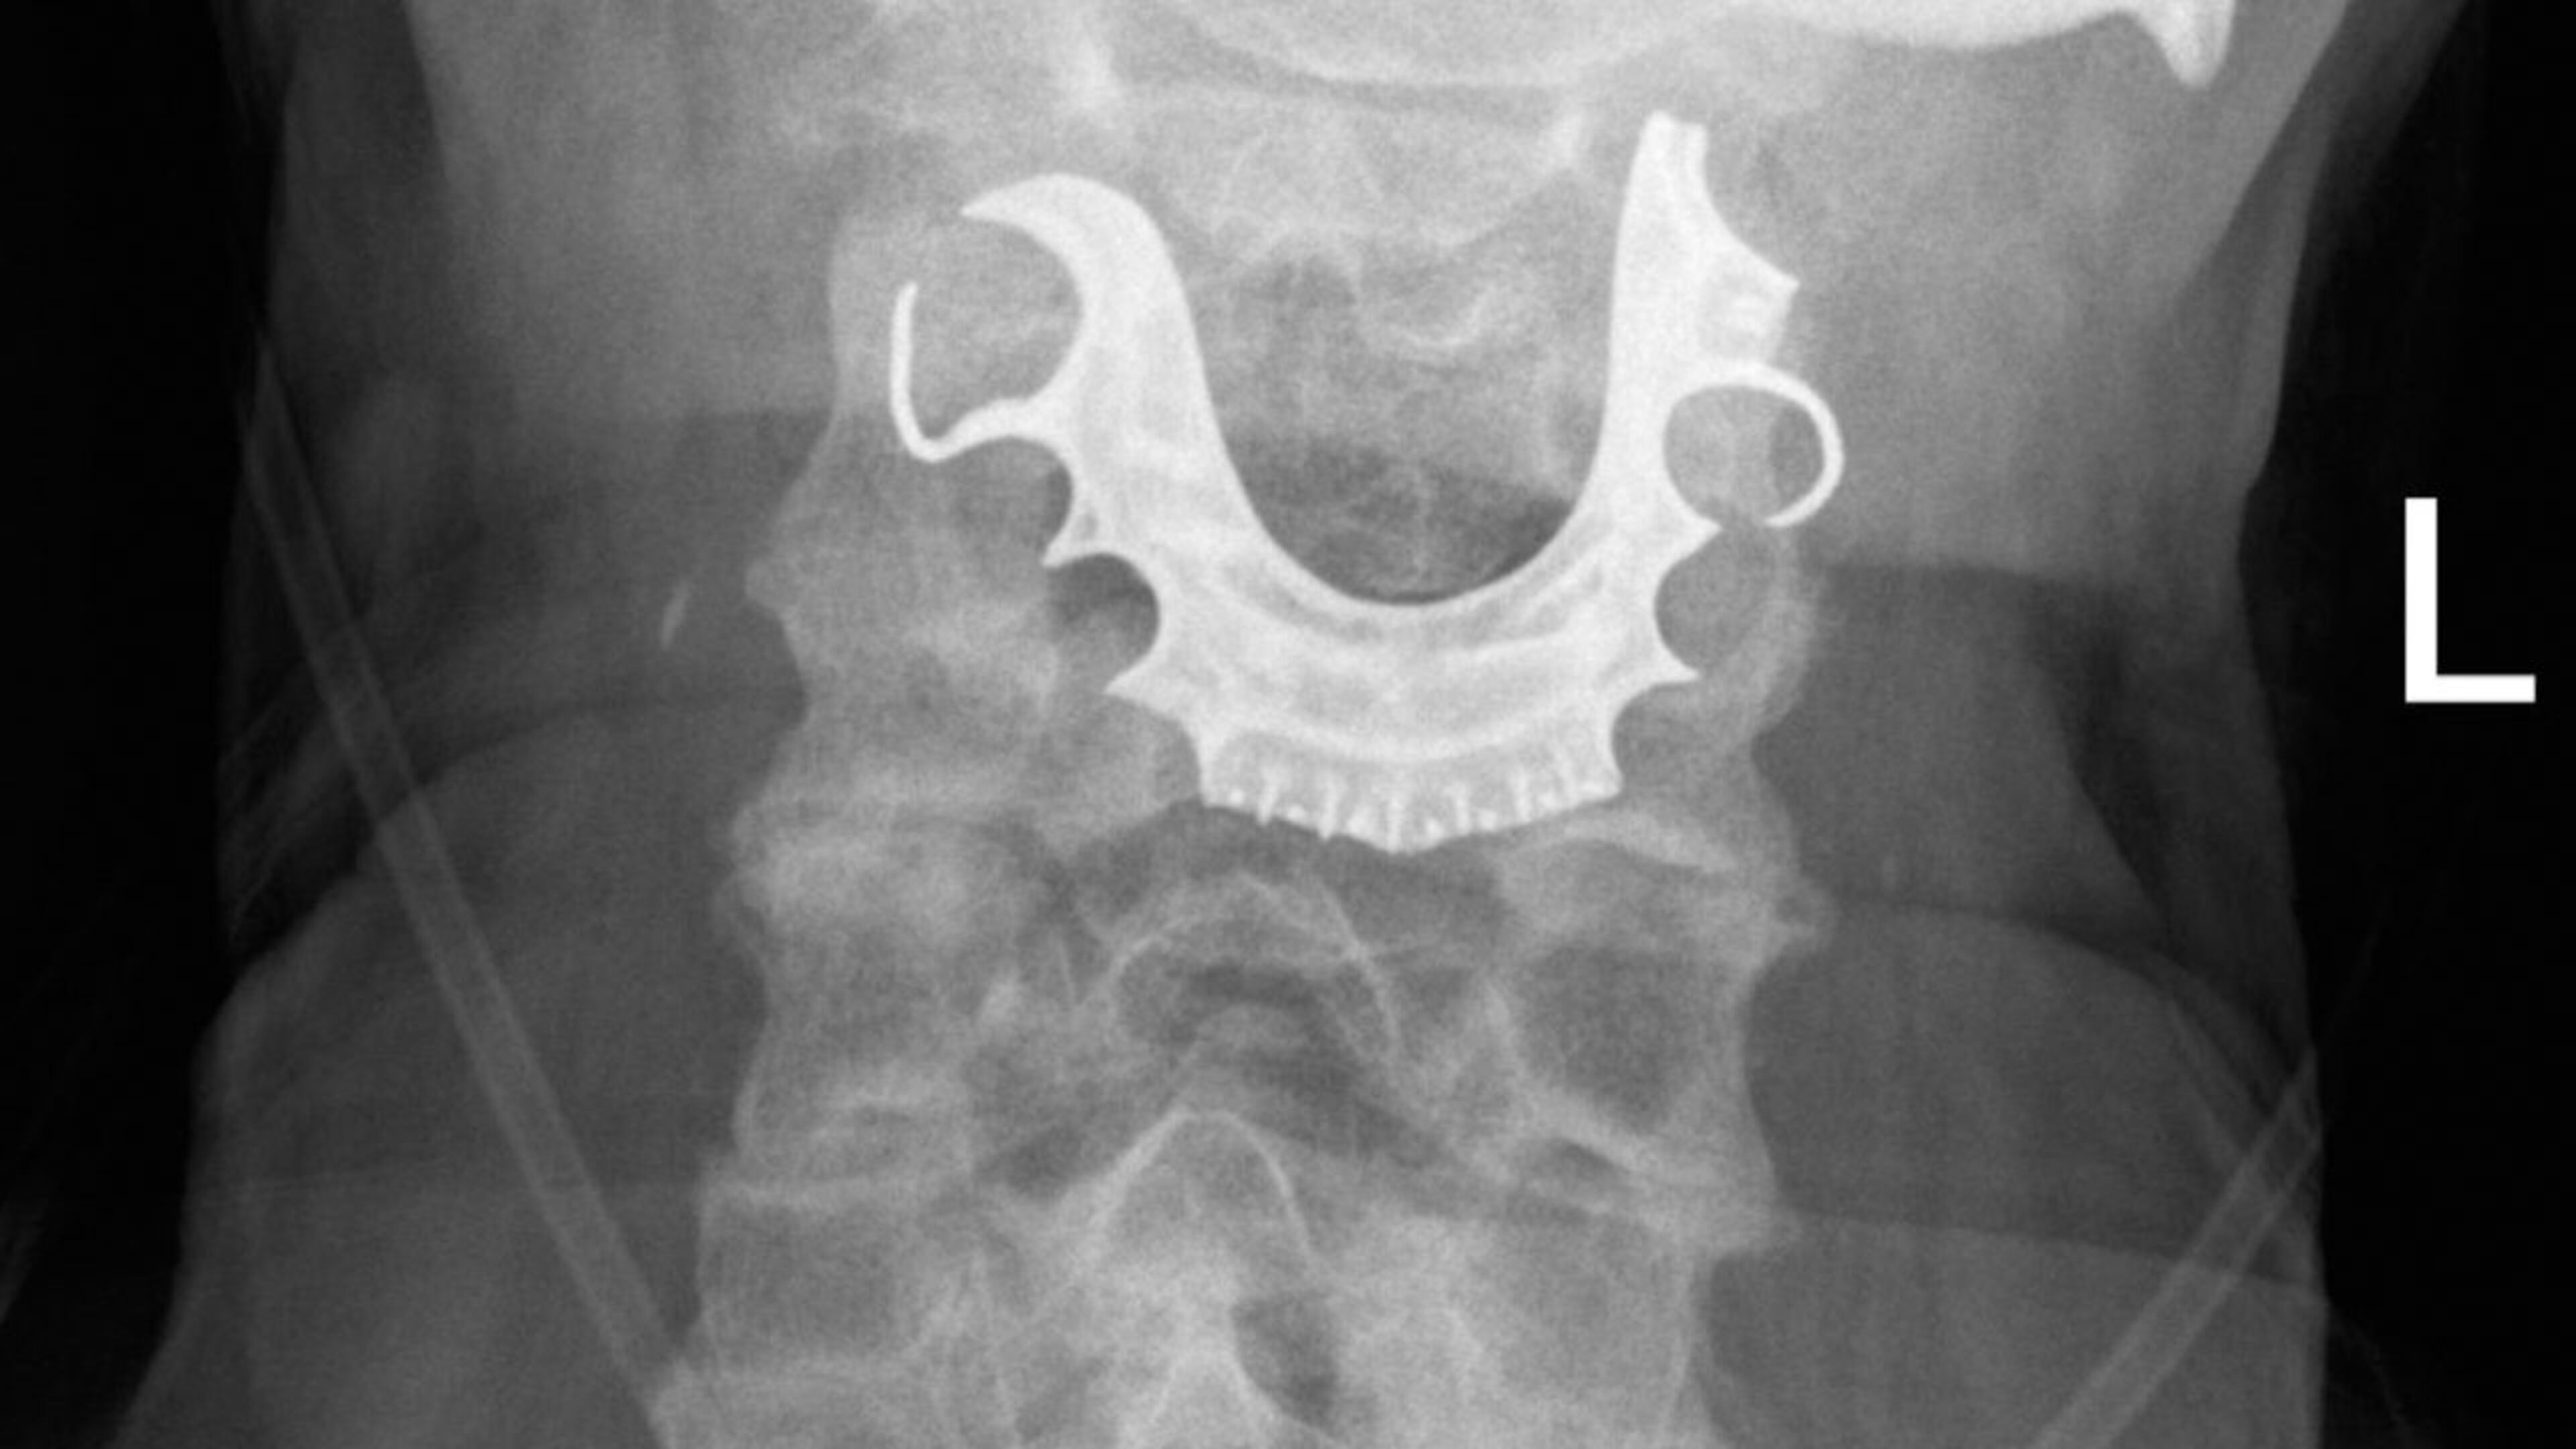

Two days later, he returned to the ER with worse symptoms and was treated for pneumonia, but a diagnostic procedure determined an object was in his larynx.

The object was the man's partial dentures.